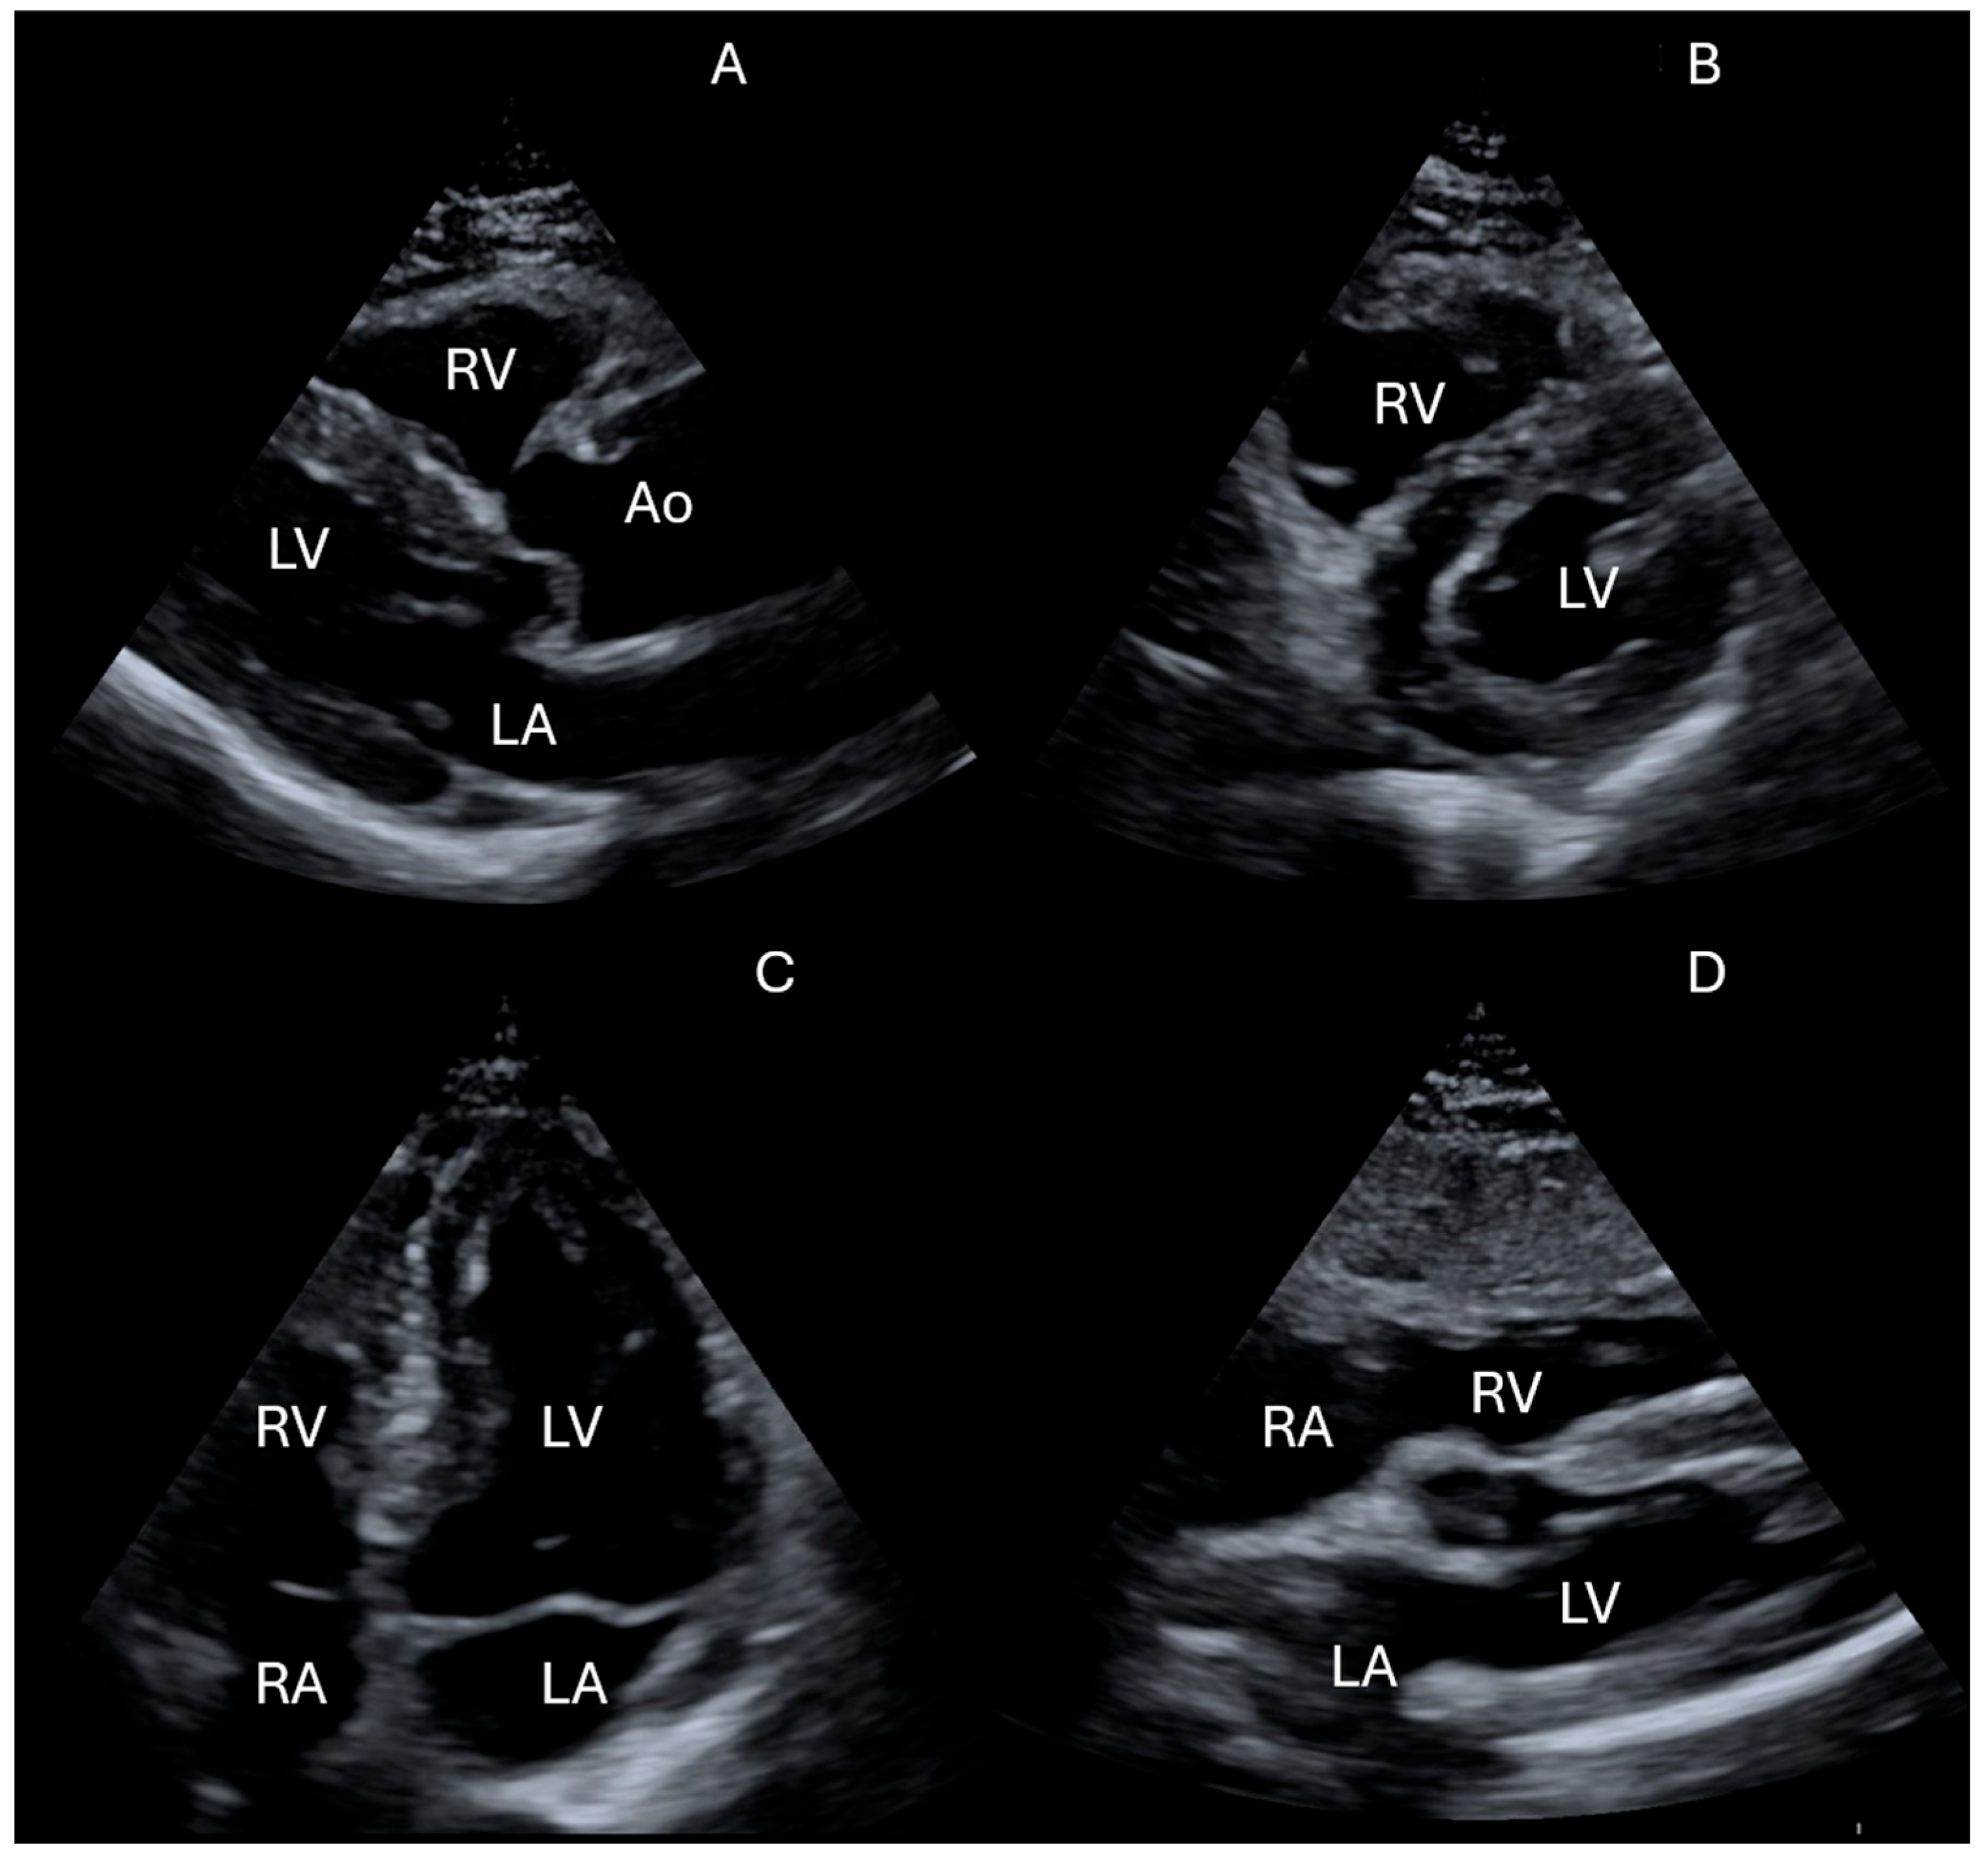

- Is there left ventricular systolic dysfunction?

- Is the IVC dilated or collapsible?

- Is there pericardial effusion or tamponade?

- Are there signs of the right ventricular strain?

- Focused Cardiac Ultrasound

- Assessment of right atrial pressure

- Lung ultrasound evaluation

- Neskovic, A.N.; Skinner, H.; Price, S.; Via, G.; De Hert, S.; Stankovic, I.; Galderisi, M.; Donal, E.; Muraru, D.; Sloth, E.; et al. Reviewers: This document was reviewed by members of the 2016–2018 EACVI Scientific Documents Committee. Focus cardiac ultrasound core curriculum and core syllabus of the European Association of Cardiovascular Imaging. Eur. Heart J. Cardiovasc. Imaging 2018, 19, 475–481. [Google Scholar] [CrossRef]

- Neskovic, A.N.; Edvardsen, T.; Galderisi, M.; Garbi, M.; Gullace, G.; Jurcut, R.; Dalen, H.; Hagendorff, A.; Lancellotti, P.; European Association of Cardiovascular Imaging Document Reviewers; et al. Focus cardiac ultrasound: The European Association of Cardiovascular Imaging viewpoint. Eur. Heart J. Cardiovasc. Imaging 2014, 15, 956–960. [Google Scholar] [CrossRef]